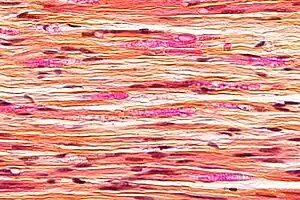

| Micrograph of a nerve with a decrease in myelinated nerve fibres (pink) and an abnormal increase in fibrous tissue (yellow), as may be seen in nerve injuries. HPS stain. | |